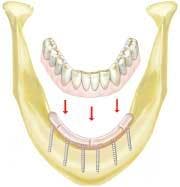

Full denture stabilization

An acrylic/metal splint can be fabricated and cemented to MTI Transitional Implants (Dentatus USA) to stabilize a maxillary or mandibular full denture. The patient's denture is retrofitted using a soft reline material. Utilizing transitional implants will also slow down the bone resorption of the ridge. The concept is reported to be a creative strategy for "jump starting" the implant aspect of a practice. The MTI transitional implants can be routinely used to provide a provisional restoration at the time of implant surgery so the patient is never without teeth, and the patient can master oral hygiene techniques before receiving the final prosthesis.

For more information, call Dentatus at (800) 323-3136.